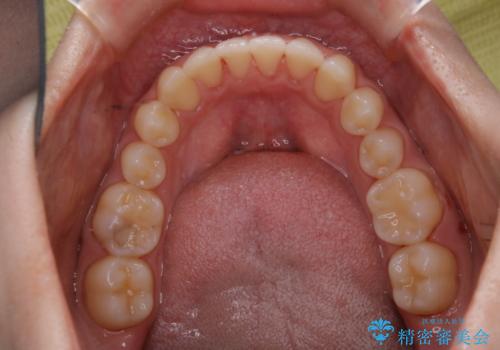

矯正治療終了後にPMTC(Professional Mechanical Tooth Cleaning)

- 矯正治療が終了したため、クリーニングでもきれいにしたいとのことでした。PMTC60分コースを行いました。

矯正治療が終わり、せっかくきれいになった歯並びも、虫歯・歯周病などになってしまっては元も子もありません。

矯正治療やセラミックなどによる被せ物の治療終了のタイミングではクリーニングを行い、汚れや着色の除去、歯と歯の間・歯と歯肉との境目などのケアをしっかりすることをおすすめしています。

ご自身での歯ブラシ・セルフケアを行うと同時に、定期的なクリーニング(PMTC)を行うことで、いつまでも健康な歯を保つことができます。